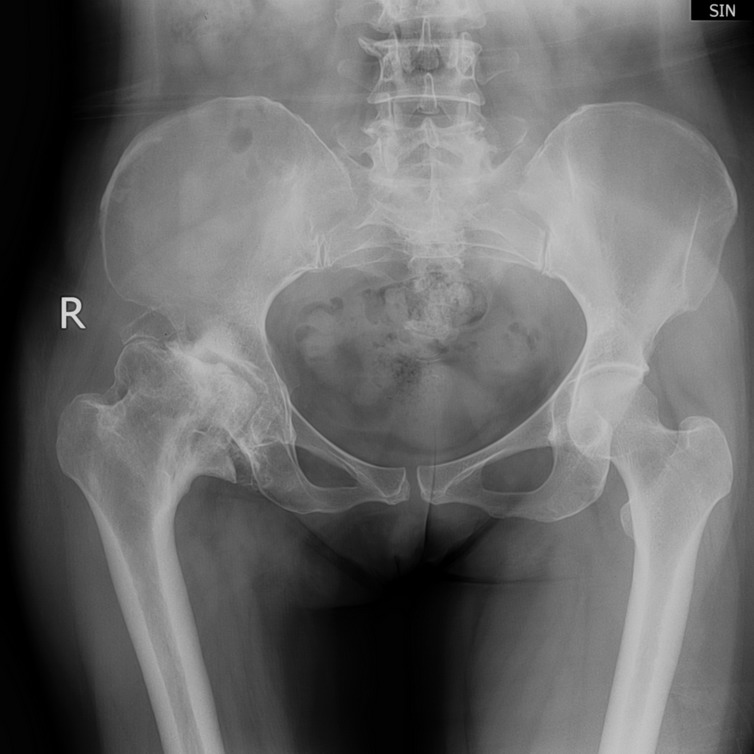

以下是引用ducky807在2008-4-19 14:08:00的发言:[br]这是一个典型的扁平髋,股骨头变扁,密度增高,内可见低密度区,考虑股骨头缺血性坏死

以下是引用jiangjing在2008-4-19 15:39:00的发言:[br]这是一个典型的扁平髋,股骨头变扁,密度增高,内可见低密度区,考虑股骨头缺血性坏死伴退行性病变或髋臼发育不良伴无菌坏死